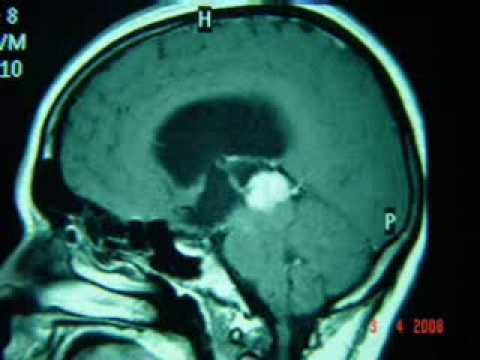

E-ISSN:2147-2181 Infratentorial Meningioma of Midline Causing Hydrocephalus: CT and MRI Findings Infratentorial Meningioma of Midline Causing Hydrocephalus: CT and ... Retrieve Full Source